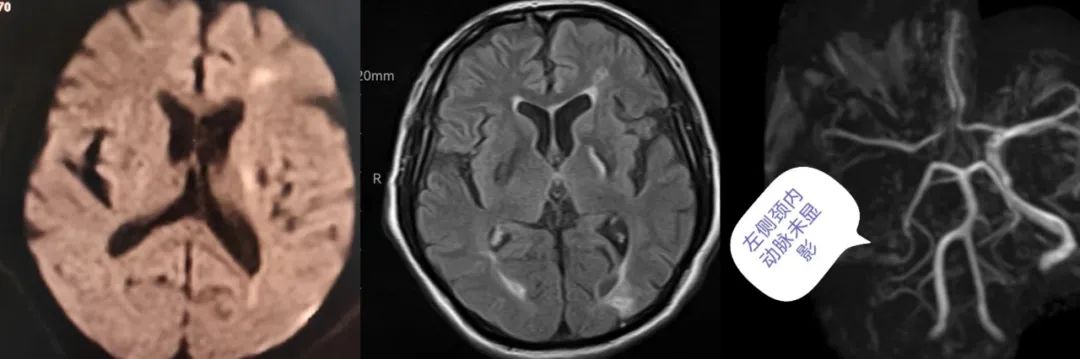

2023年12月15日下午,胡大爷的老伴发现丈夫一觉醒来不仅讲不出话来,右半边身体还基本不能动,随后赶紧将他送往陕西省中医医院就诊。抵达医院急诊科,医生查看询问患者病史,初步考虑为脑卒中。为了确保患者的生命安全,医疗处副处长屈小元和脑病医院院长惠振亮紧急协调相关科室,立即启动卒中救治绿色通道,完善头颅CT、MRI检查,诊断为急性脑梗塞,左侧颈内动脉闭塞。患者嗜睡、失语,右侧上肢肌力0级,右下肢肌力2级,情况十分危急。

据家属描述,患者凌晨3点入睡前一切正常,中午12点醒后右侧肢体无力,15点不能讲话、右侧肢体基本不能动。结合患者的病史和发病情况,医生判断胡大爷属于典型的醒后卒中,神经外科王宏主任医师和脑病一科陈钧主任医师综合评估病情和风险,考虑为左侧颈动脉闭塞引起的急性脑梗塞,由于患者发病时间长,超过静脉溶栓的时间窗,若不及时手术,出现大面积脑梗死,将会导致严重残疾,甚至随时会有生命危险。

医生当机立断,“必须立刻准备取栓!”与胡大爷的家属充分沟通后,家属同意手术治疗,随后迅速将患者送入导管室。术中脑血管造影显示,左侧颈内动脉闭塞,卒中中心介入团队利用抽吸导管,成功取出暗红色的血栓,颈内动脉眼段重度狭窄,用球囊予以扩张成形,使患者闭塞的血管得到及时的再通,血流恢复正常。目前胡大爷语言、右侧肢体肌力恢复正常,已经行走着出院。